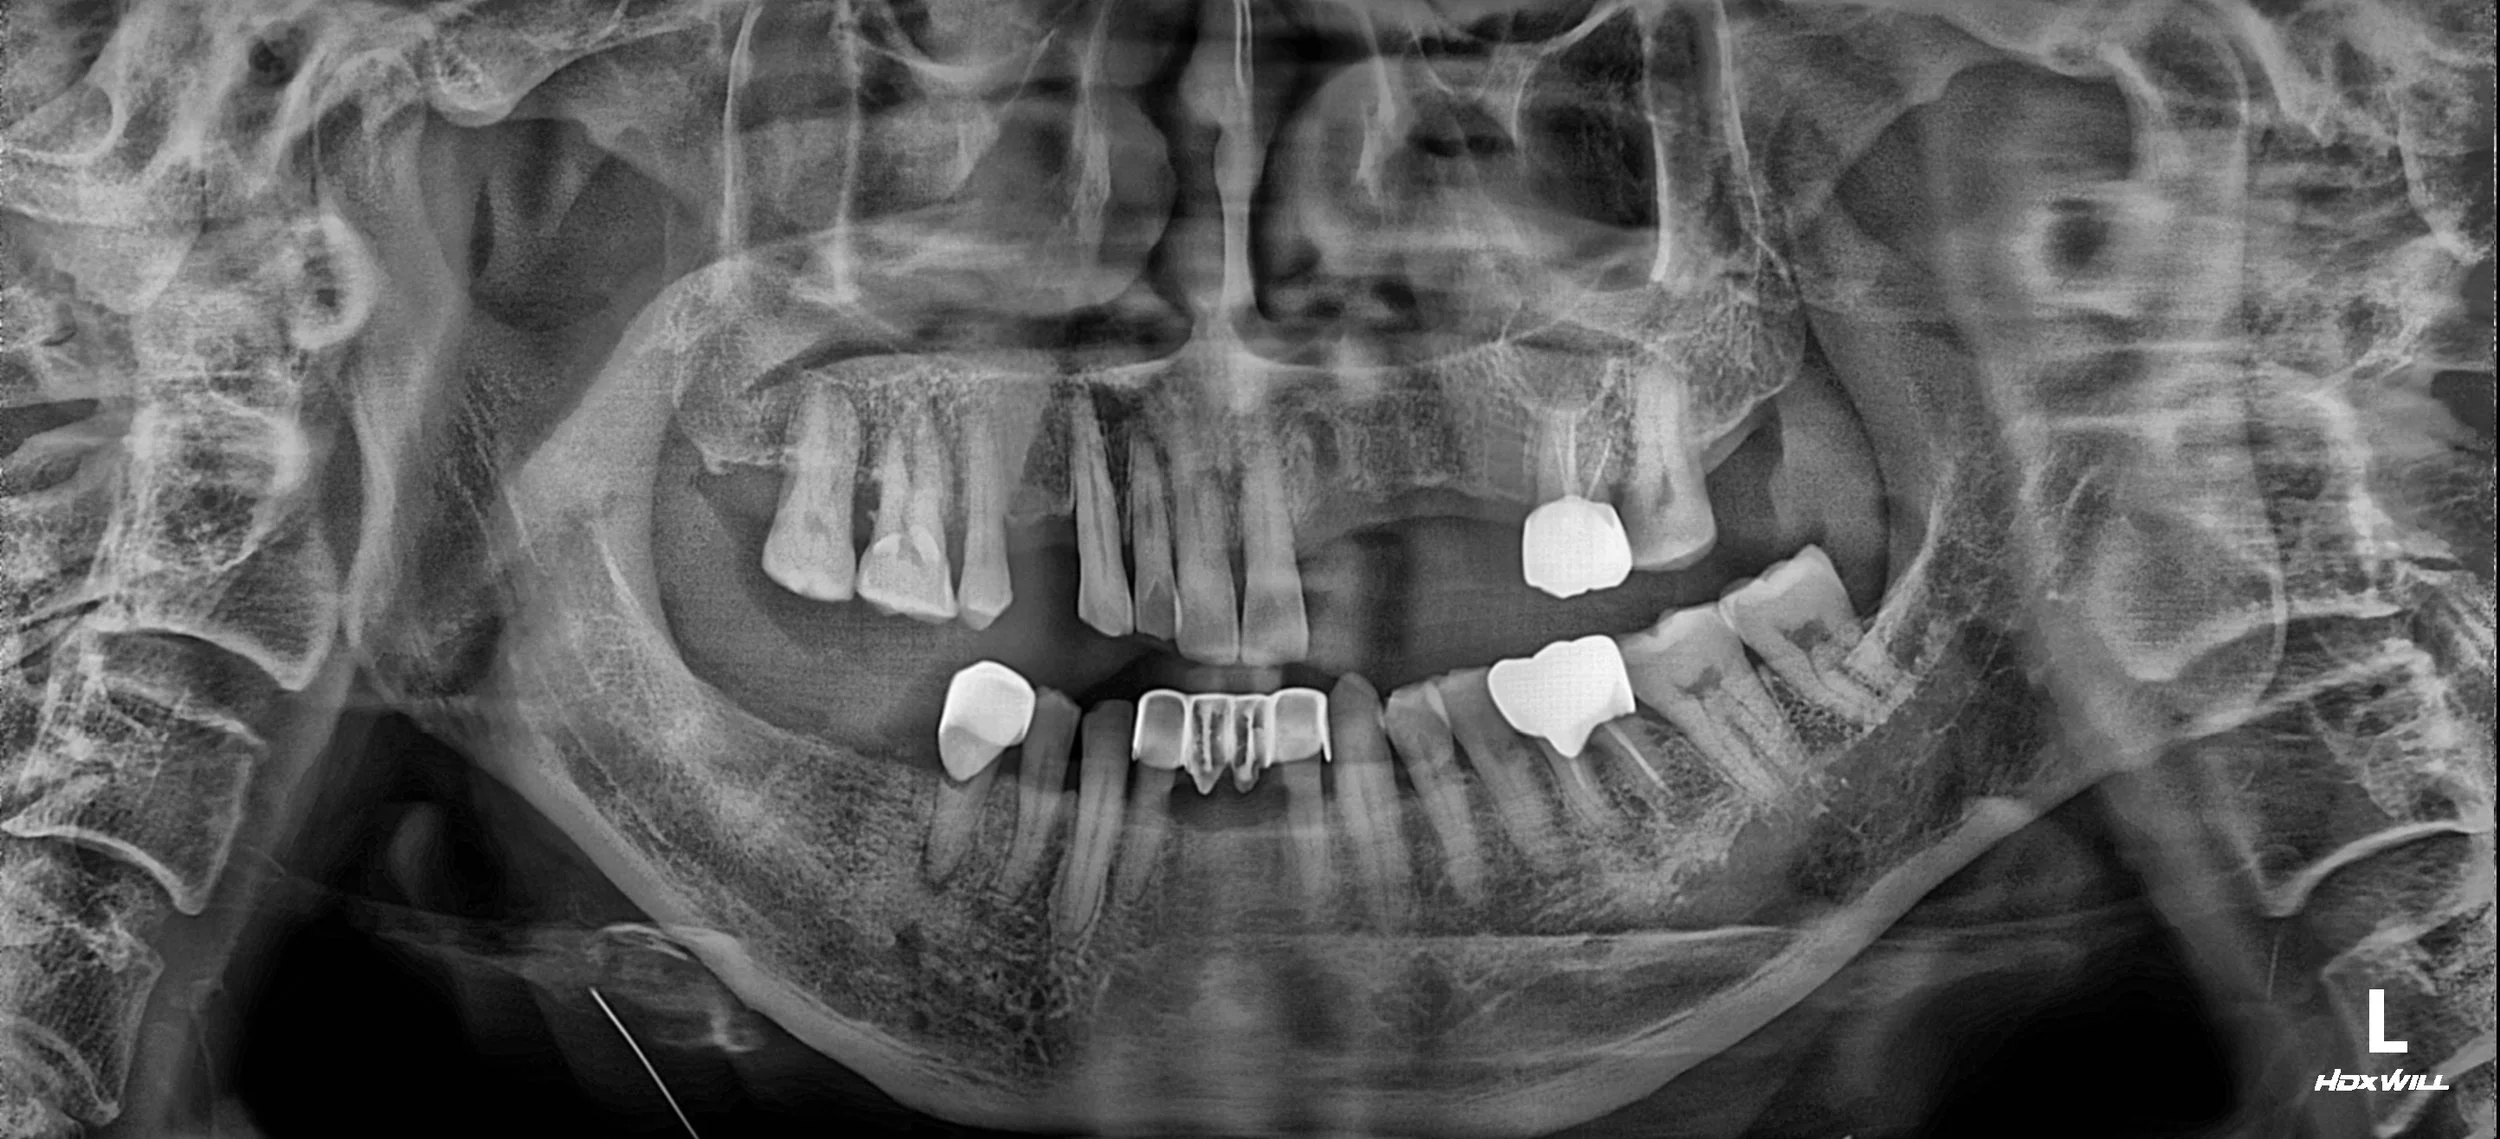

OPG - BEFORE

1. Occlusal Plane Re-establishment: Posterior support was re-established through strategic implant placement and crown restorations. By elevating the Vertical Dimension of Occlusion (VDO), we were able to "unlock" the trapped mandible.

2. Mandibular Repositioning: As the occlusal height was lifted, the mandible was guided to a more posterior and physiologically stable position. This effectively reduced the severity of the anterior deviation.